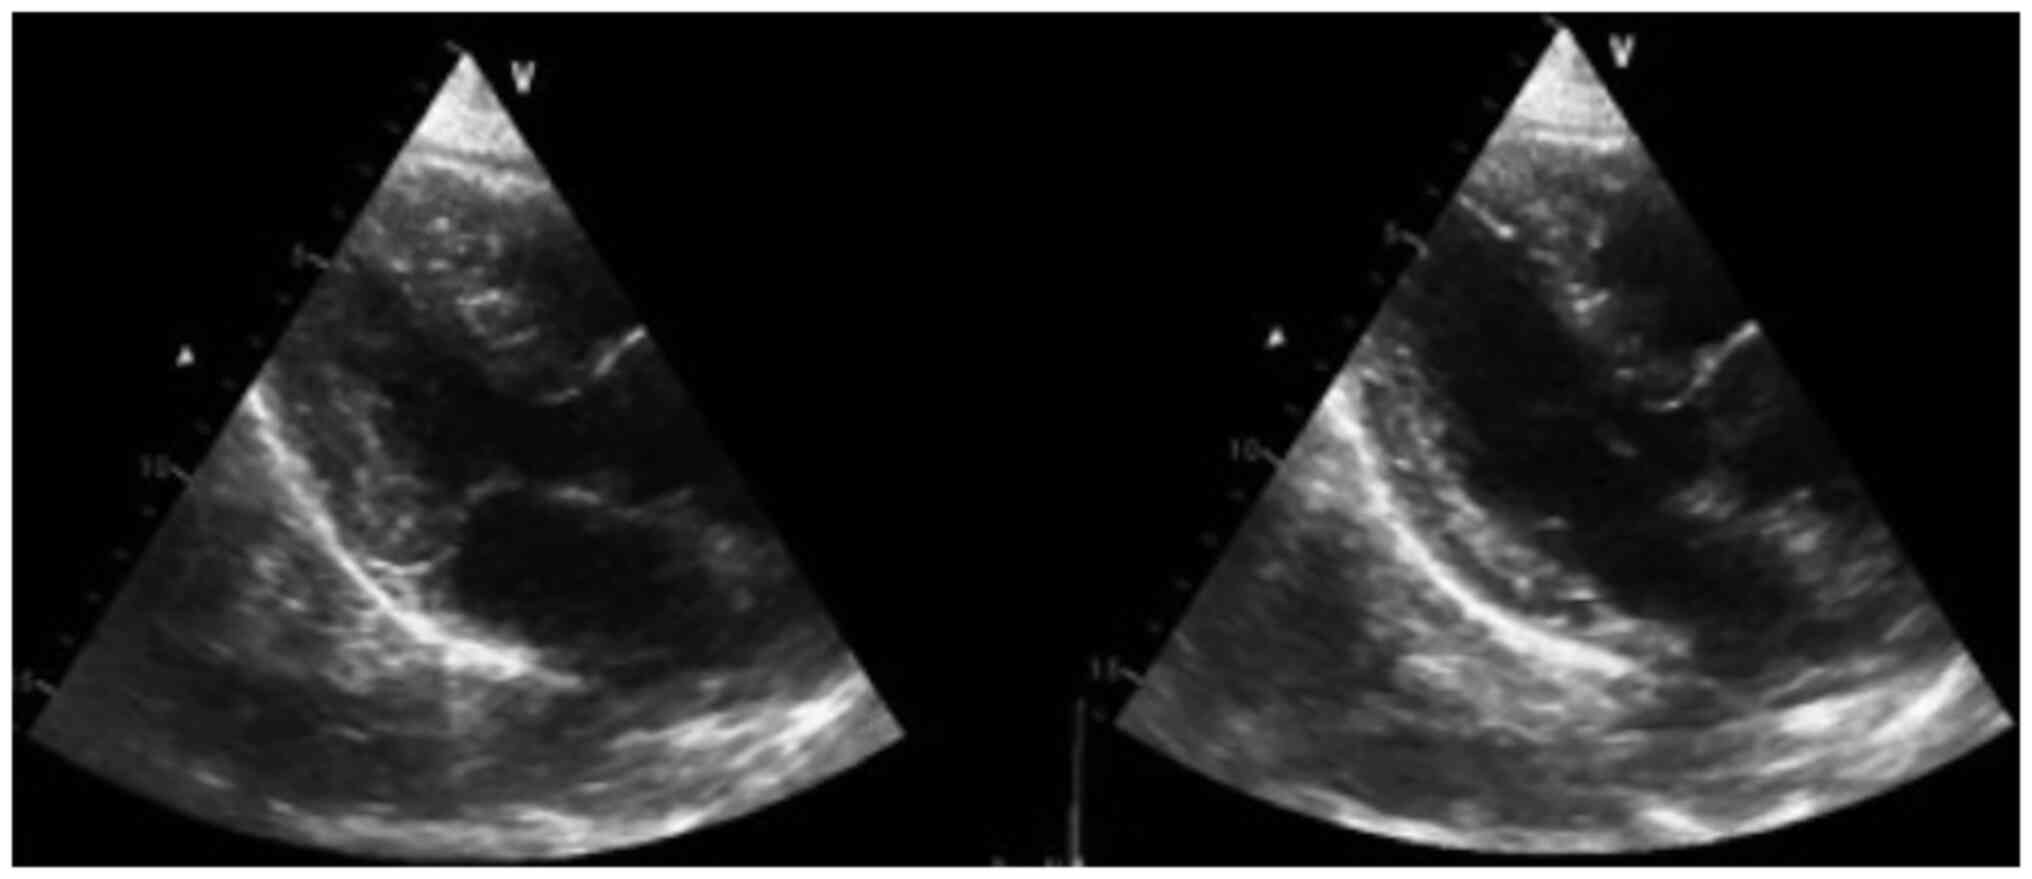

After 6 h, the patient was admitted to Hospital San Vicente Fundación (Rionegro, Colombia), a highly complex hospital (a hospital with the infrastructure, technology and specialists that allow it to provide the population with a health service that treats the most complex diseases), where the following vital signs were recorded: Blood pressure, 184/83 mmHg (hypertensive); heart rate, 52 beats per minute (bradycardia); respiratory rate, 22 breaths per minute tachypneic; and oxygen saturation, 97% (normal value). On physical examination, the patient was drowsy and oriented in three spheres. Muscular strength was 5/5 in the right half of the body and 4/5 in the left upper limb without alteration in sensitivity, aphasia or dysarthria. The patient denied symptoms including chest pain, angina, dyspnea, limitation in functional class, palpitations and previous cardio and neuromuscular events. Acute neurovascular syndrome was suspected, for which a simple skull tomography was performed, revealing spontaneous IPH of the right basal ganglion in the context of an acute cerebrovascular accident of hypertensive origin without any criteria for neurosurgical surgical intervention; furthermore, the patient did not require reversal of the administered antiplatelets. Fig. 4 reveals a right temporal intraparenchymal hematoma with vasogenic edema and ventricular involvement without any changes compared with the previous one. Fig. 5 suggests no akinesia or hypokinesia, but diastolic dysfunction and relaxation disorders are present.

Figure 5

Transthoracic echocardiogram (taken 24 h after admission). The image suggests no akinesia or hypokinesia, but diastolic dysfunction and relaxation disorders are present; no signs of ischemia, intracavitary masses or thrombi were observed (left panel: Parasternal long axis cut-systole; right panel: Parasternal long axis cut-diastole).

The patient was hospitalized in the intensive care unit for a hypertensive brain emergency and required a vasodilator for 2 days (nitroglycerin and IV labetalol). A transthoracic ECG was performed, revealing an ejection fraction of 65% (calculated using Simpson's method) with type I diastolic dysfunction due to relaxation disorders and without signs of ischemia, intracavitary masses or thrombi (Fig. 5).